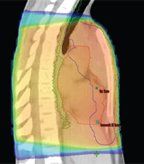

FIGURE

Color-Wash Dose Distribution for Three Plans for a Representative Patient With Mediastinal Involvement of Hodgkin Lymphoma

PT reduces high-, medium-, and low-dose radiation levels compared with 3DCRT. Dosimetric studies evaluating the use of PT in HL date back to 1974, when Archambeau et al explored the use of PT for total nodal irradiation.[29] In that study, the investigators demonstrated that PT could reduce the irradiated volume by 50% compared with photons. More sophisticated treatment planning studies have since been published. In a prospective phase II study of involved-node radiotherapy in patients with mediastinal HL,[30] the first 10 patients enrolled underwent treatment planning with 3DCRT (AP/PA), IMRT, and PT and were offered treatment with the plan that best spared the organs at risk while maintaining appropriate target coverage. In all 10 cases, PT was associated with the best plan and all patients were offered treatment with PT. The Figure shows the color-wash isodose distributions for the 3DCRT, IMRT, and PT plans for one of these patients. The Table describes the expected dose-volume effects from EFRT (mantle radiation) using 3DCRT, from IFRT using 3DCRT, from INRT using 3DCRT, from IMRT, and from PT; these data demonstrate the considerable dose reductions achieved with each successive treatment approach.